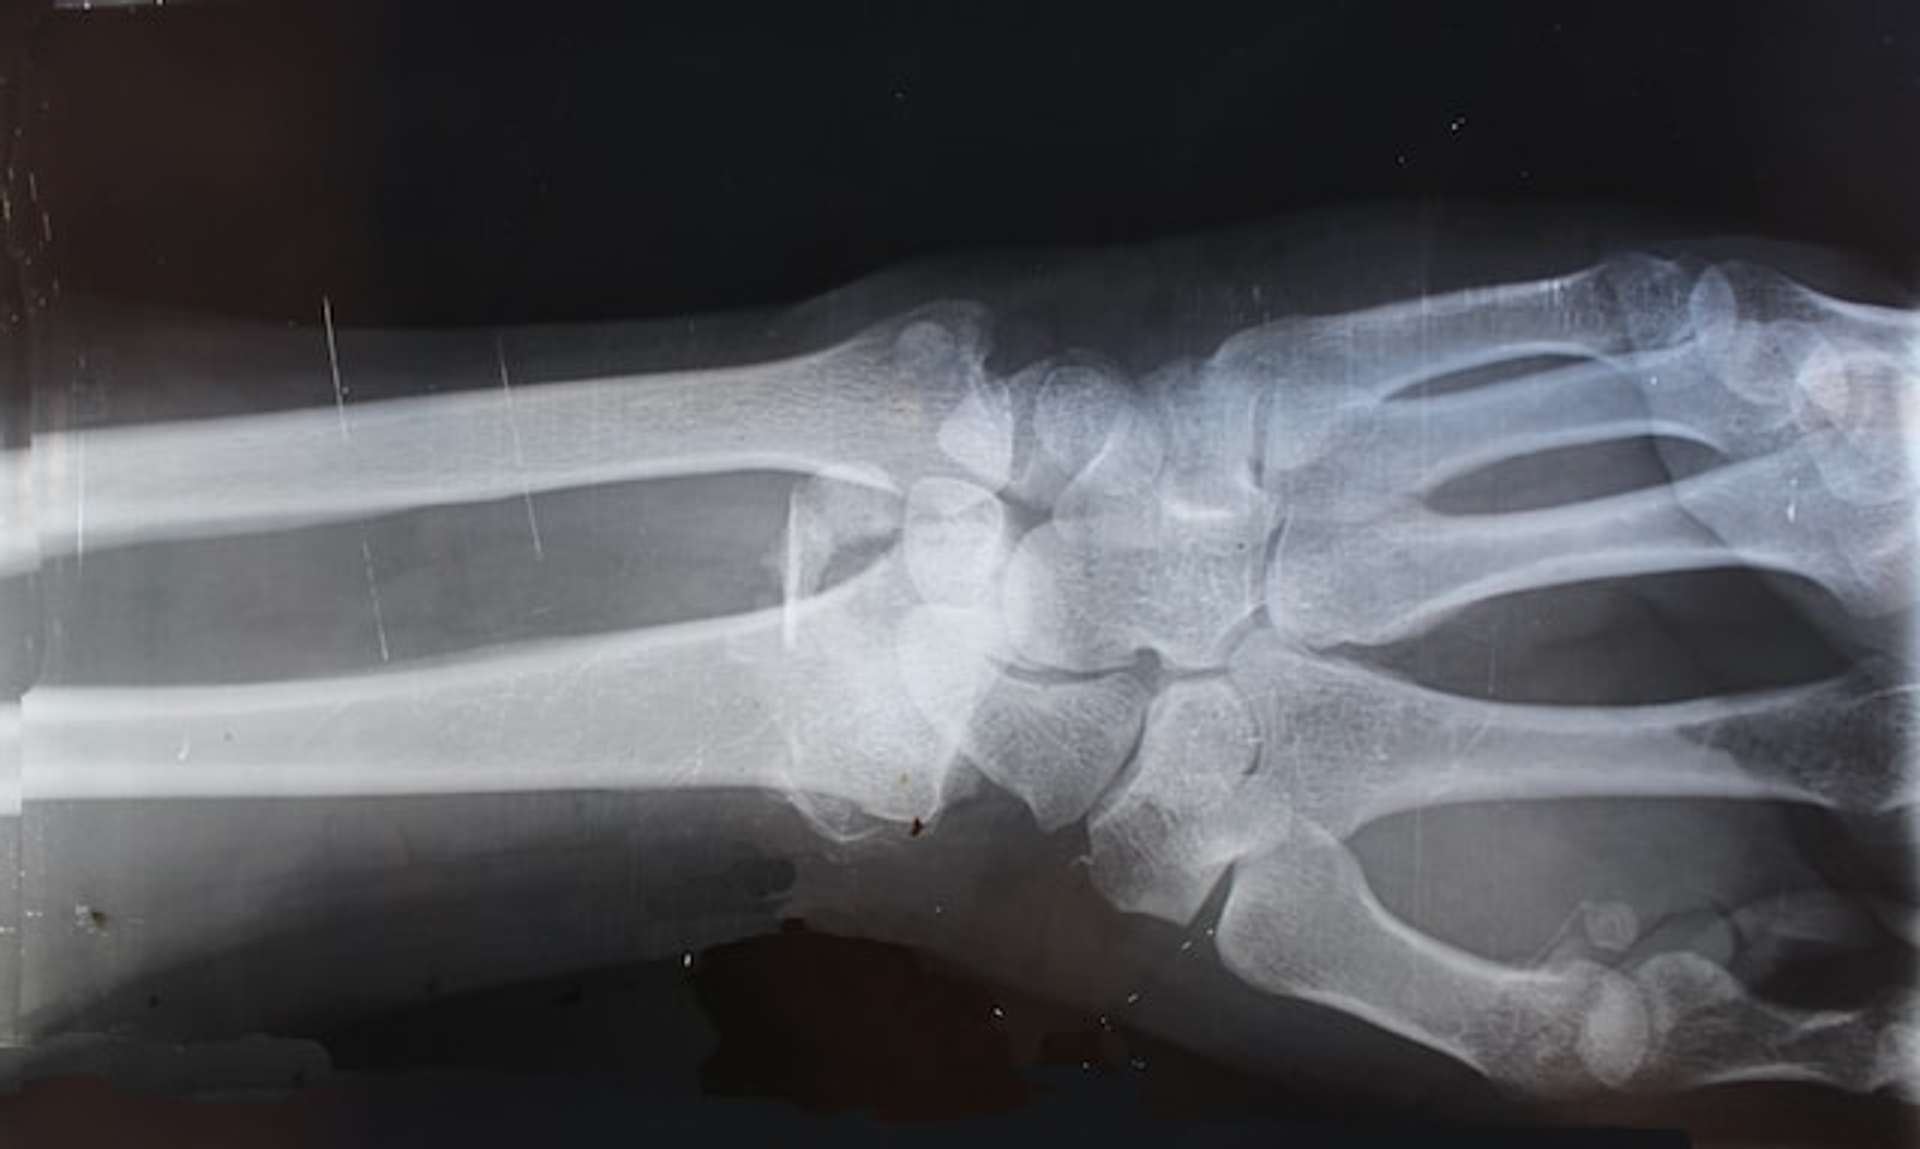

In Lumon Labs, a human hand was grown for the first time. It took a lot of hard work to develop and cultivate the bone, muscle, and skin tissues, but we did it.